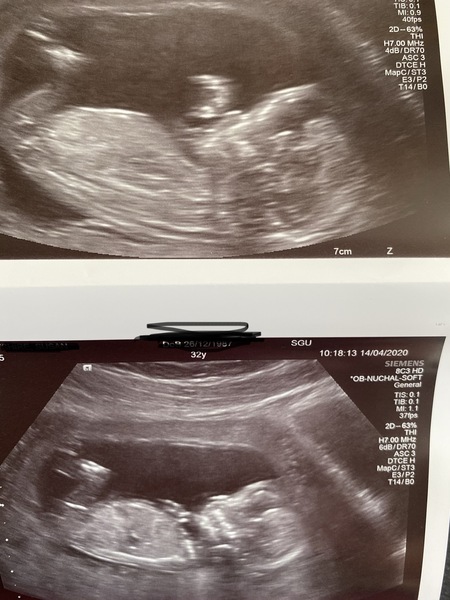

Thank you all for your such nice messages, and being such a great support network to me and everybody else in this thread ❤️ I realised I didn’t add my scan photo.